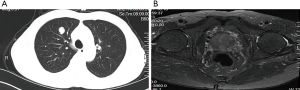

In October 2016, a 74-year-old male non-smoker presented to our hospital for a physical examination, which revealed a pulmonary mass. A computed tomography (CT) scan showed a mass in the right lower lung (Figure 1). The patient had non-special comorbidities, family and psycho-social history. The patient was given treatment options and chose observation. A repeat contrast-enhanced CT one week ago in our hospital showed a nodule in the right upper lobe of the lung with malignant signs, which was considered to be primary lung cancer. Tumor biomarker testing showed the following: alpha fetoprotein (AFP), 2.48 ng/mL; carcinoembryonic antigen (CEA), 2.64 ng/mL; ferritin, 141.0 ng/mL; squamous cell carcinoma-associated antigen, 0.60 ng/mL; carbohydrate antigen, 199 <2.00 IU/mL; free PSA, 0.6 µg/L; and total PSA, 3.0 µg/L. The patient underwent a thoracoscopic radical resection of the right upper lung with electrocautery division of pleural adhesions under general anesthesia. The post-operative pathology findings were as follows: tumor cells: CK5/6 (–); CK7 (–); P63 (–); CK20 (–); TTF-1 (–); Napsin A (+); Ki-67 (+,30–40%); Syn (–); CgA (–); CDX-2 (+); PSA (+); and P504S (+) (Figure 2). Then, a next generation sequencing (NGS) analysis of the tumor biopsy identified that the tumor had TP53 p.V216M, NF1 c.3974+1G>A, CD274, CDK6, PIK3CA, SOX2, PREX2 and RICTOR amplification (3D Medicines, Shanghai, China) Based on hematoxylin-eosin staining and immunohistochemistry, the tumor met the criteria for a poorly differentiated adenocarcinoma (approximately 1.8 cm in diameter) and was likely metastatic from a primary prostate tumor. A prostate magnetic resonance imaging (MRI) suggested prostatic space-occupying lesions involving the seminal vesicles bilaterally (Figure 1), with a high possibility of prostate cancer. Needle aspiration biopsies of the prostate gland were then obtained and the pathologic examination confirmed prostate adenocarcinoma with a Gleason grade score of 4+4=8 points (prognostic grade group IV). The patient was treated with one subcutaneous injection of leuprolide (3.75 mg) and endocrine therapy [oral bicalutamide (50 mg qd)] as first-line therapy until now. During almost 3 years of follow-up since the first administration of endocrine therapy, every-3-month PSA evaluation and digital examination confirmed the status of disease was stable (Figure 3). This patient tolerated and adherent to the endocrine therapy quite well except grade 1 appetite and pubic hair loss, respectively.